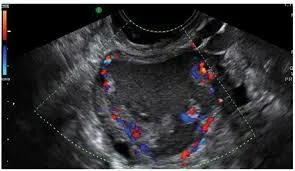

- Ultrasound: Low positive predictive value for cancer